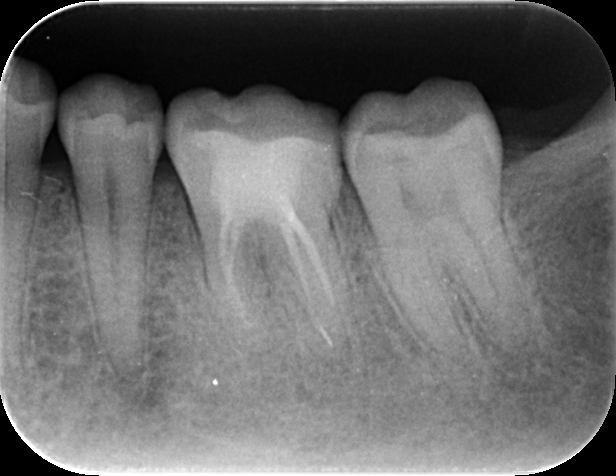

症例 下顎左側第一大臼歯予防的歯内療法 2025.09.10 主訴:海外赴任するため、根管治療をしっかり行い、セラミックの被せ物でやり直したい 背景:症状はないものの、脱離を繰り返す銀歯のやり直しと、精密根管治療を希望し当院へ 数ヶ月後に海外赴任を考えると、可及的速やかに歯内療法療法を終える必要性があった 状態:根尖病変は認めないが、不良な治療後であったため、説明と同意を得た後、歯内療法を行い セラミック修復を終えた 治療前デンタル 治療後デンタル 治療回数:2回 治療時間:各90分 治療費用:料金表参照 治療担当:野田哲朗 この記事のタイトルとURLをコピーする